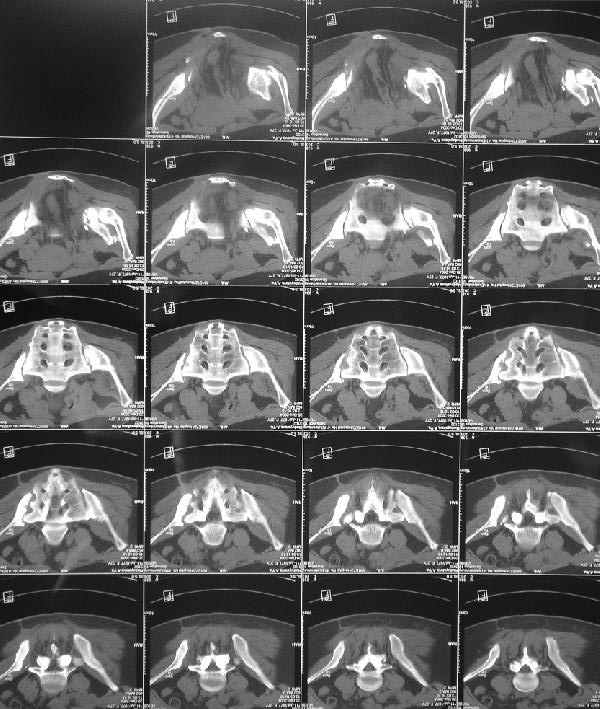

Дополнительно сообщаю, что больную беспокоят боли в области левого крестцово-подвздошного сочленения, в области правого болей нет. Кроме того, беспокоит укорочение конечности (ходит с компенсацией) без дополнительной опоры (в помещении), нарушение осанки (сколиоз, избыточный поясничный лордоз), боли в пояснице, невозможность стоять более 20-30 минут, спать без резинового круга под крестцом и подушкой под коленями, неудобство при сидении. Majeed 41 балл.

По просьбам коллег отправляем снимки таза: прямая, inlet, outlet, 2 дополнительные компьютерные томограммы.